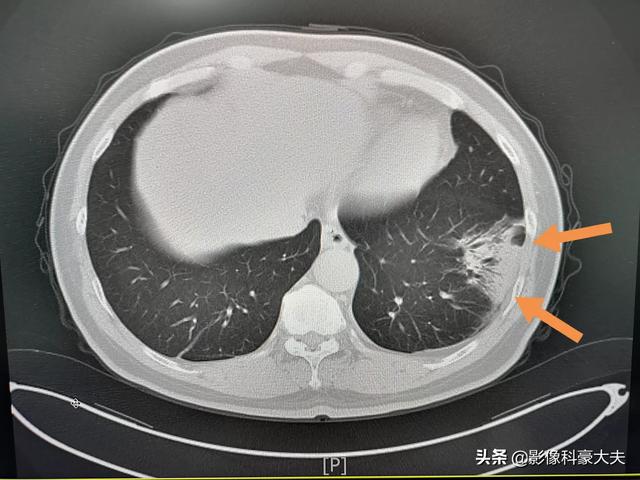

Cet homme d'âge moyen, qui toussait et avait de la fièvre depuis trois jours, présentait au scanner une pneumonie inférieure gauche, répartie le long du sous-segment, avec une densité relativement élevée (pas d'ombre de verre dépoli), et des signes d'insufflation bronchique étaient observés du côté hilaire des poumons, accompagnés d'une augmentation de la numération sanguine, ce qui en faisait une pneumonie banale, et non un coronavirus.

Il a été traité avec des antibiotiques et s'est considérablement résorbé au bout de 9 jours :

2. avec des caractéristiques d'imagerie de pneumonie :Cela signifie qu'il y a des changements inflammatoires dans les poumons, présentant de multiples petites ombres en taches et des changements interstitiels, qui sont évidents dans les bandes externes des poumons, et même des changements tels que de multiples ombres en verre dépoli et des ombres d'infiltration dans les deux poumons. Vous vous demandez peut-être pourquoi il y a des changements d'imagerie dans les poumons après une infection. C'est principalement parce qu'une fois que le virus a envahi les poumons, il peut provoquer une congestion et un œdème dans les poumons, qui se traduisent par des ombres de haute densité sur la radiographie ou la tomodensitométrie.

②La tomodensitométrie thoracique peut suggérer de multiples ombres parcellaires et des changements interstitiels au stade précoce, et elle est évidente dans les bandes extrapulmonaires, et l'examen ultérieur développe de multiples ombres en verre dépoli et des ombres d'infiltration dans les deux poumons, et dans les cas sévères, des lésions pulmonaires solides apparaîtront.

②. Le thorax présente les caractéristiques d'imagerie d'une pneumonie.

Au stade initial, elle présente de multiples petites taches et des changements interstitiels, qui peuvent évoluer vers de multiples taches en verre dépoli et infiltrées dans les deux poumons et, dans les cas les plus graves, des changements solides dans les poumons peuvent se produire, ce qui donne ce que l'on appelle communément les "poumons blancs".